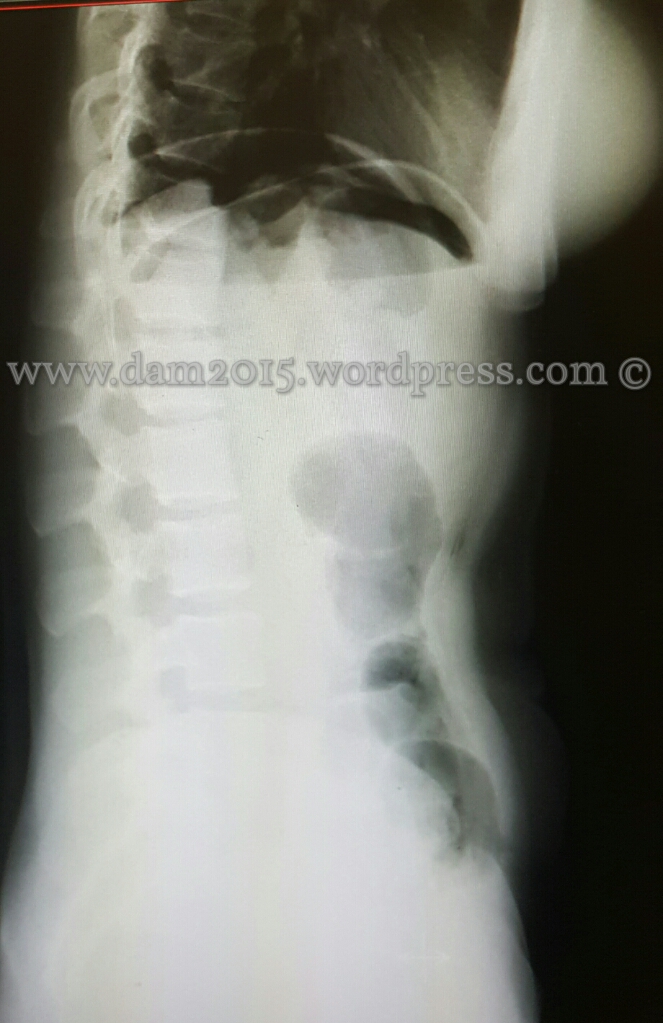

Paziente donna, 41 anni.

Addome acuto da perforazione gastrica in seguito a ulcera peptica.

Alla RX diretta dell’addome visibile falce d’aria sottodiaframmatica come da perforazione di viscere cavo.